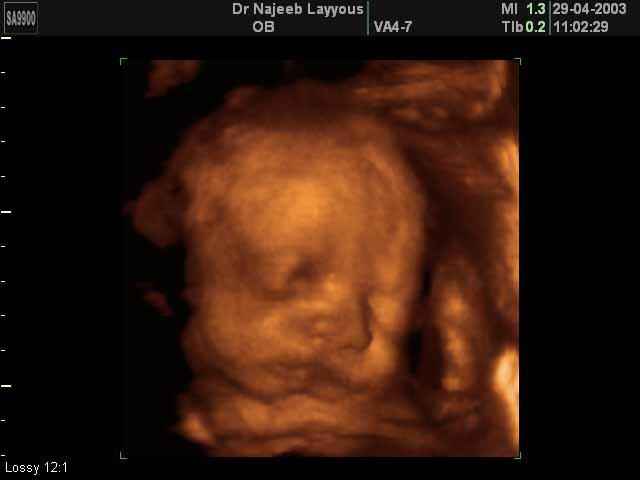

- صور لوجه الجنين في داخل الرحم

صور لوجه الجنين بجهاز الالتراساوند ثلاثي الأبعاد | الدكتور نجيب ليوس